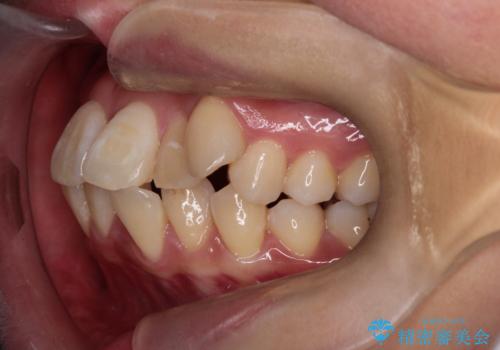

- 八重歯(叢生)と、上下の歯の中心線(正中)がずれていることを主訴にご来院されました。精密な検査の結果、歯列全体のスペースが大幅に不足しており、八重歯を正しい位置に配列し、正中のズレを改善するためには、上下左右の第一小臼歯を抜歯する必要があると診断。装置には、目立ちにくい審美ワイヤーを使用し、見た目を気にせず、機能性と審美性が完璧に整った咬み合わせを目指す治療計画を立案しました。

八重歯: 突出していた八重歯を歯列内に誘導し、デコボコを解消しました。

正中のズレ: 歯を左右対称に移動させることで、上下の歯の中心線を正確に合わせ、顔全体のバランスも改善しました。